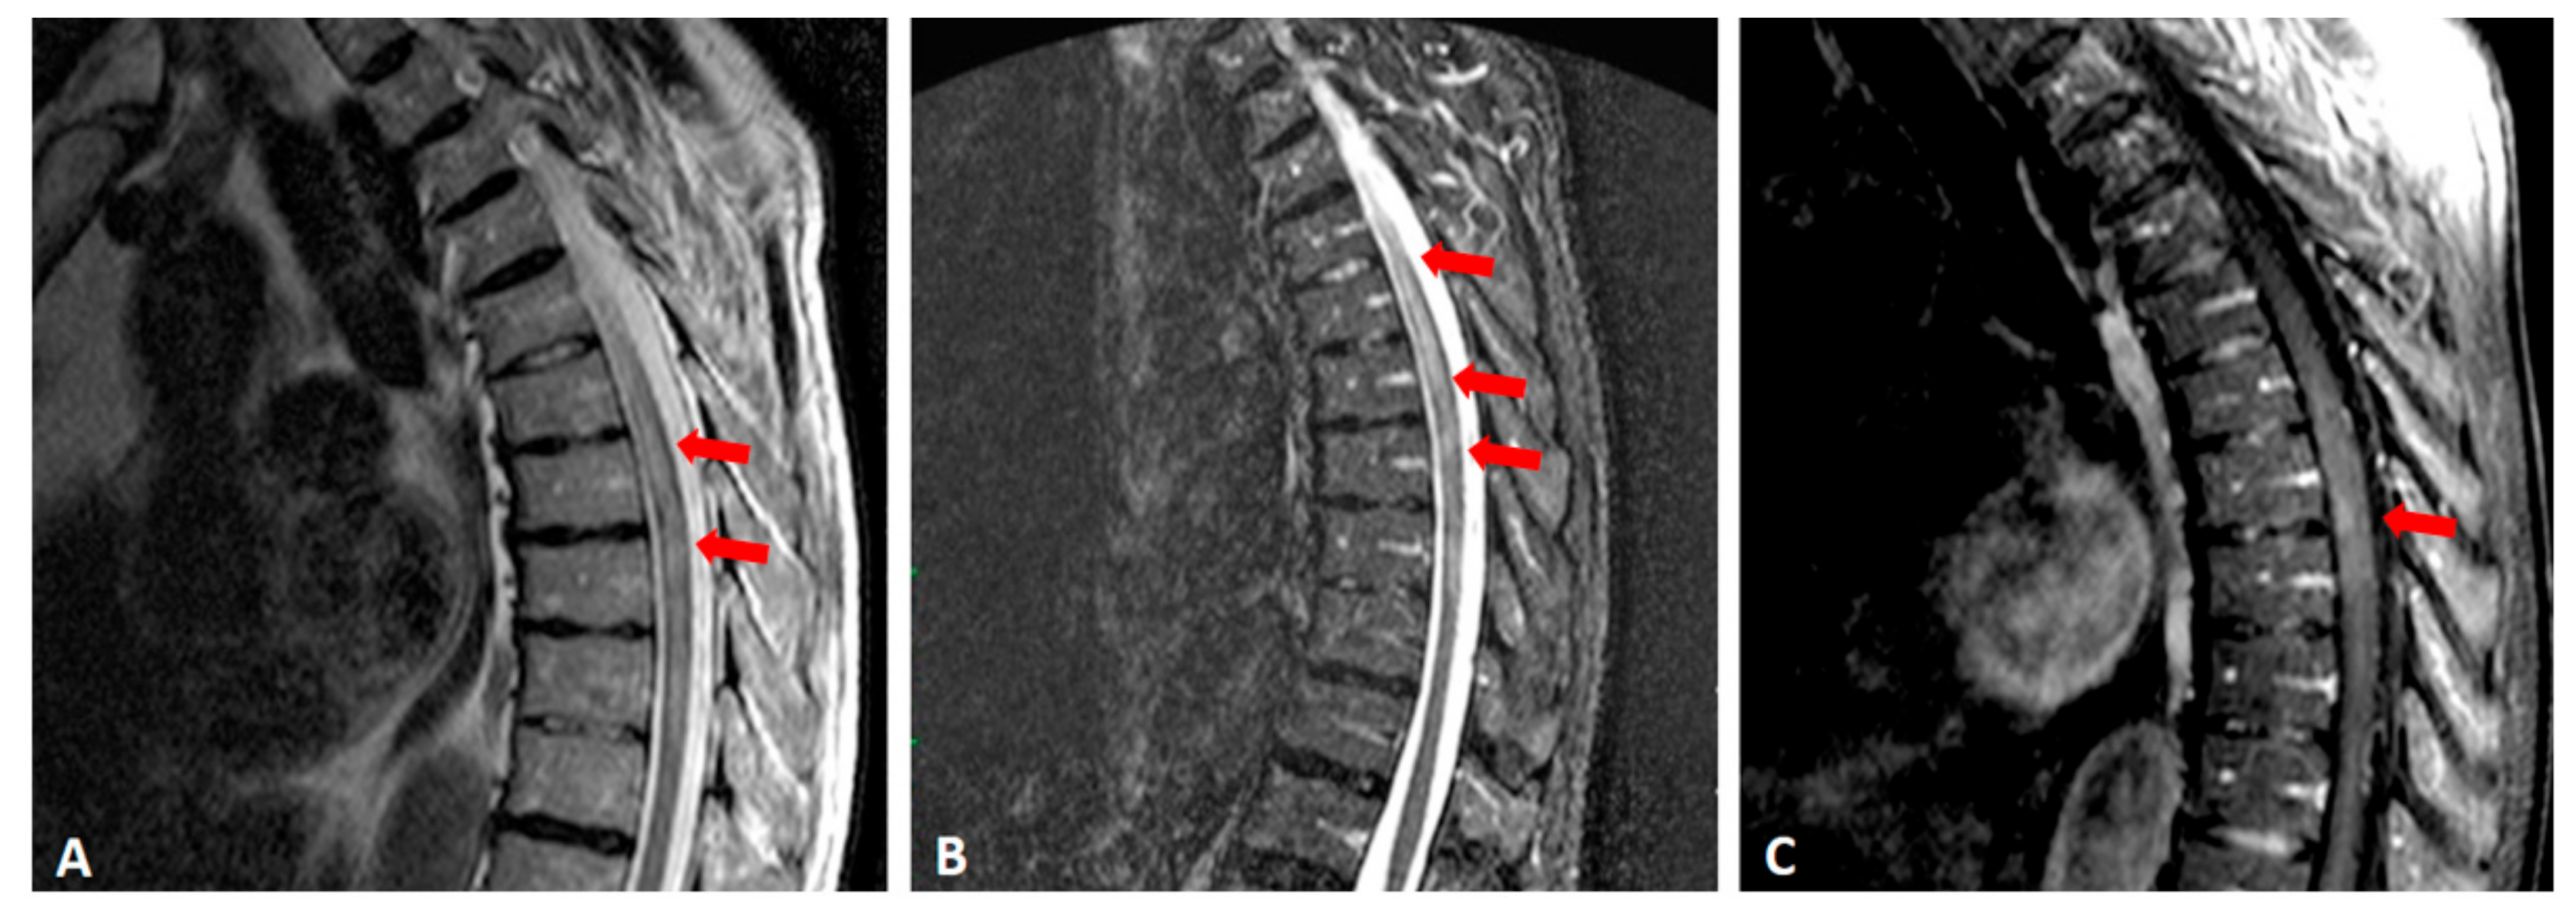

2. Case Presentation